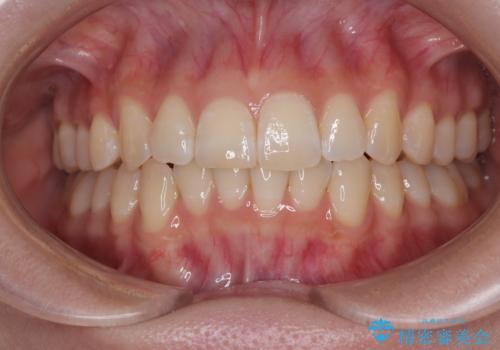

- 上下前歯の重なりを気にして来院された患者様です。

安価なインビザラインパッケージを用いての治療を希望されており、デコボコの程度が中等度であったため、インビザライン・モデレートを用いて矯正治療を行うこととしました。

インビザライン・モデレートは、製作できるアライナーの枚数に制限があるため、移動可能な量に限りがあるものの、インビザライン・ライトよりも枚数が多いため、幅広い症例に対応可能です。